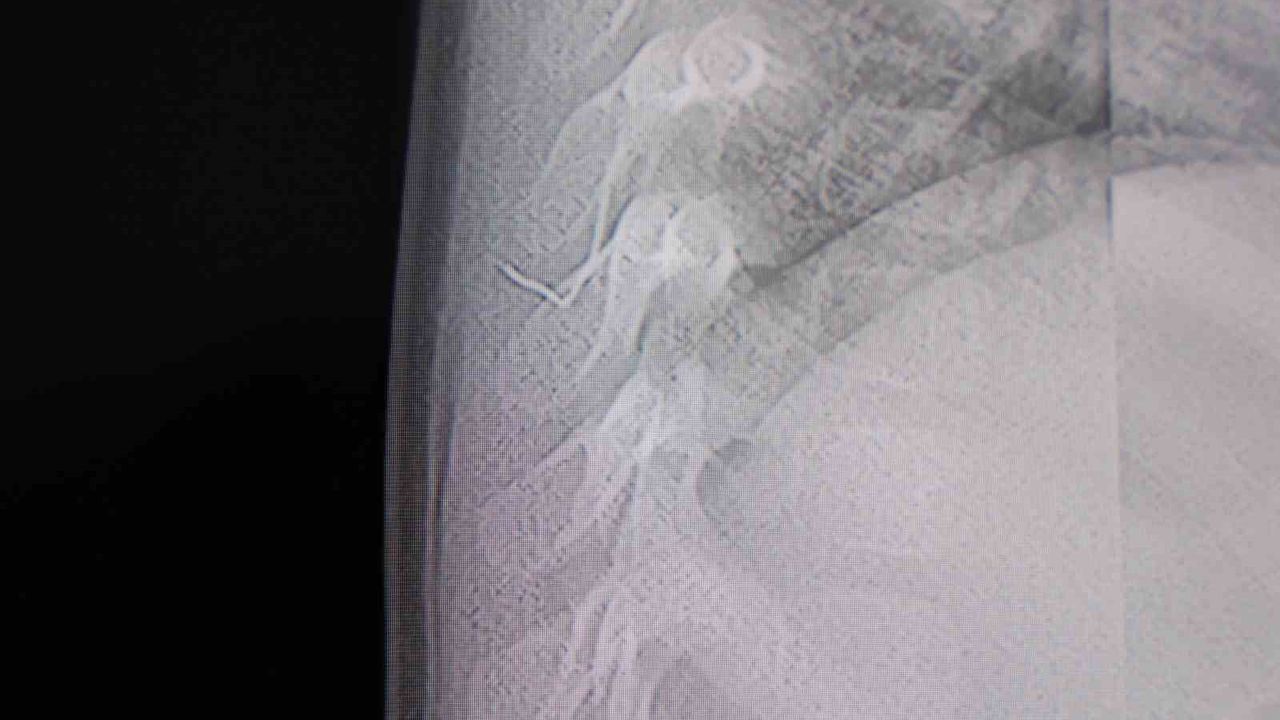

Alınan bilgiye göre, Kahramanmaraş'ta farklı ortopedi, çocuk cerrahisi ve beyin cerrahisi kliniklerine başvurusu yapılan bir yaşındaki bebeğin, sırt bölgesinde yabancı bir cisim olduğu ancak müdahalenin zor olduğu ve 8 yaşına kadar beklenmesi gerektiği bildirildi. Aile, bebekleri için son olarak HG Hospital'e başvurdu. HG Hospital Beyin ve Sinir Cerrahisi Uzmanı Prof. Dr. İdris Altun tarafından yapılan tetkiklerde, yabancı cismin cilt altında, omurilik kanalına yakın bir bölgede olduğu ve akciğer zarına doğru ilerlediği belirlendi. Hasta, genel anesteziye alınmadan, lokal anestezi ve sedasyon eşliğinde ameliyata alındı. Yapılan müdahalede yabancı cisim tamamen çıkarıldı. Çıkarılan cismin, ince zımba teline benzer metal bir tel olduğu ve yaklaşık 2 santimetre uzunluğunda bulunduğu tespit edildi. Hasta, aynı gün taburcu edildi.

Konuya ilişkin açıklama yapan Prof. Dr. İdris Altun, 'Sırtında yabancı bir cisim olduğu söylenmiş ancak çıkarılamayacağı ve 8 yaşına kadar beklenmesi gerektiği ifade edilmişti. Bize başvurduğunda yaptığımız tetkiklerde, cilt altında, omurilik kanalına çok yakın ve akciğer zarına doğru ilerleyen bir yabancı cisim tespit ettik. Hastamızı tamamen uyutmadan, lokal anestezi ve sedasyon eşliğinde müdahale ederek lezyonu tamamen çıkardık. Çıkardığımız cismin ince zımba teline benzer, yaklaşık 2 santimetre uzunluğunda metal bir tel olduğunu gördük. Bu yabancı cisim alınmasaydı, bölgede enfeksiyon gelişebilirdi. Enfeksiyon sonucu omurilik kanalında ciddi hasarlar oluşabilir, çocuk büyüdükçe cismin hareket etmesine bağlı olarak omurilikte zedelenmeler meydana gelebilirdi. Ayrıca yana doğru ilerleyerek akciğer zarına ve akciğere batma riski vardı. Bu da enfeksiyona ve ilerleyen süreçte tümörle karışabilecek tablolara neden olabilirdi. Şu an hastamız gayet sağlıklı. Gerekli kontrolleri yaptık ve aynı gün taburcu ettik' dedi.